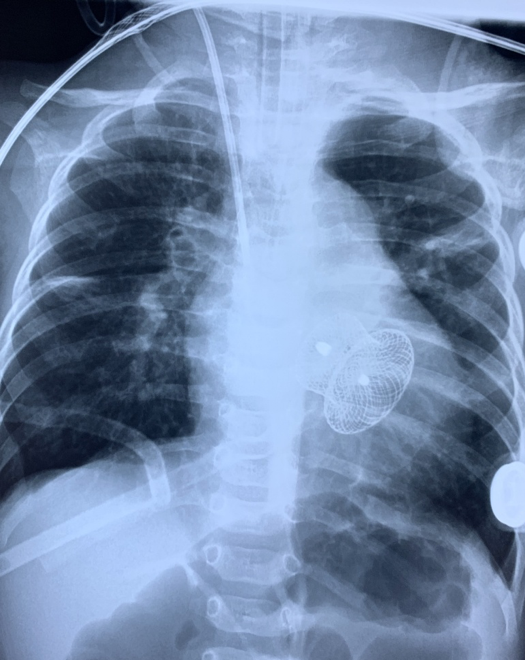

Phim chụp ngực bệnh nhi trước và sau ca phẫu thuật. Ảnh: BVCC. |

Bệnh nhi được gây mê toàn thân, mổ mở qua đường xương ức. Sau đó, phẫu thuật viên sử dụng dù để bít lỗ thông liên thất. Kết thúc ca mổ, các bác sĩ chụp buồng tim và siêu âm tim, tháo dụng cụ, dây dẫn. Bước cuối cùng, đội ngũ y tế cầm máu và đóng xương ức.

Giai đoạn hậu phẫu gây nhiều khó khăn cho các bác sĩ do T. bị tăng áp lực động mạch phổi và suy dinh dưỡng. 7 ngày sau, T. được rút máy thở. 2 tuần tiếp theo, bé xuất viện.